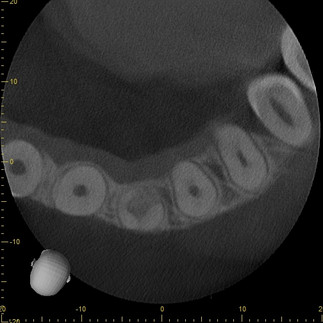

At first glance, the PA appears to show internal resorption on 10. The CBCT that was acquired on this patient (using the J. Morita X800 F40) shows a different situation:

The CBCT scan made clear that this was actually a more rare case of internal resorption that had progressed into replacement resorption. Progressing through the scan, you can actually see that the bone has regrown in such a way that it has completely separated the crown from the apex of the tooth, fundamentally changing the treatment plan for this patient.

The combination of three slice perspectives and the ability to adjust the orientation of the volume allows for a far more comprehensive understanding of pathology or anatomical anomalies.